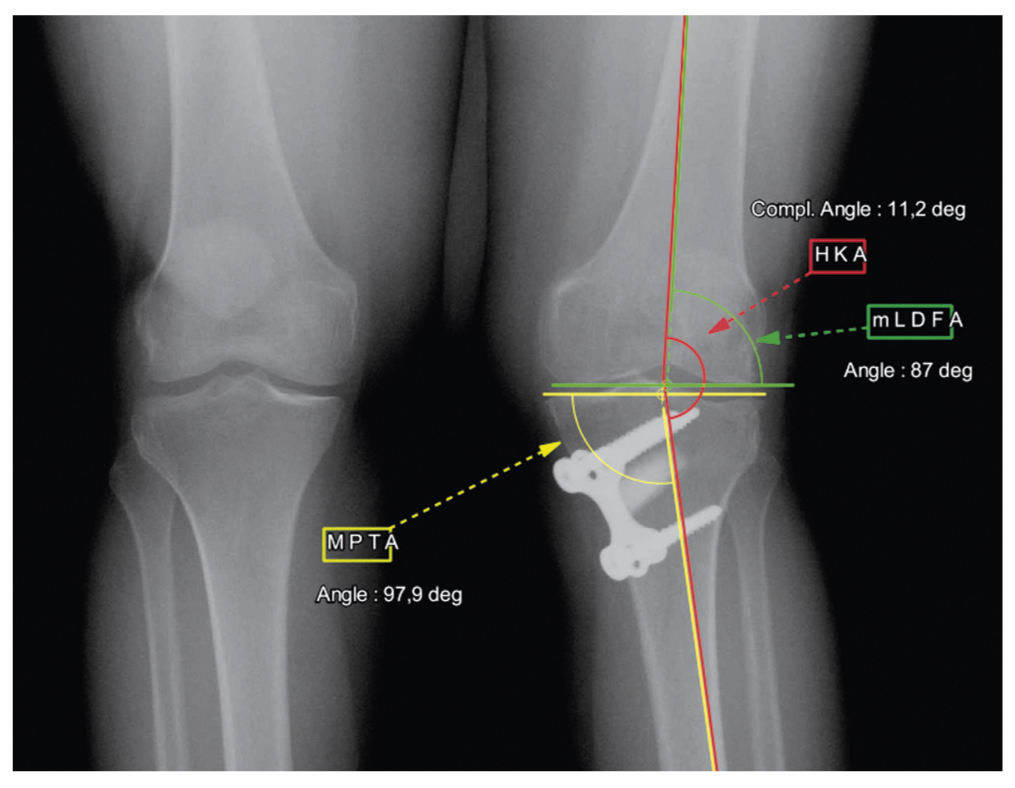

Спустя 6 мес ревизионного вмешательства мы получили следующий клинический и функциональный результат: KOOS 92 балла, AOFAS 99 баллов, боль в коленном и голеностопном суставе по шкале ВАШ — 1 и 1 см соответственно. По данным топограммы определялась вальгусная деформация коленного сустава 3°, угол MPTA — 88,4° (рис. 4).

Рис. 4. Топограмма нижних конечностей после ревизионной высокой тибиальной остеотомии. / Fig. 4. A topogram of the lower extremities after revision high tibial osteotomy.

Ось голеностопного сустава была компенсирована до нормальных значений TPI и TI — 4,4° и 4,8° соответственно. Визуально отсутствовала грубая деформация левой нижней конечности, объем сгибания составил до 115°, дефицита разгибания не отмечено.